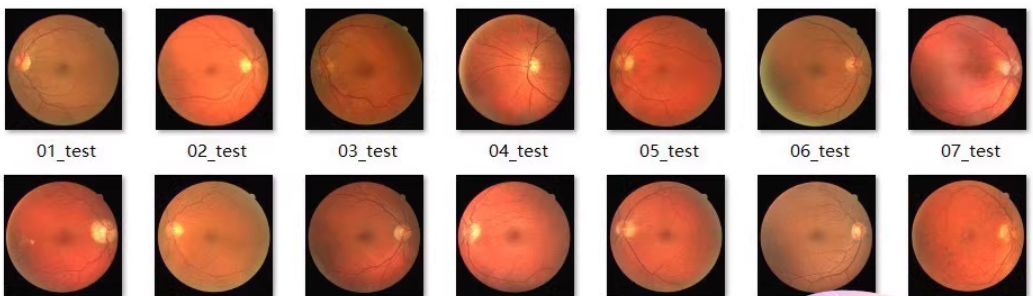

收集和标注眼底血管图像数据集,用于训练UNet模型进行图像分割。常用的公开数据集有DRIVE、STARE等。

数据预处理

对数据进行预处理,包括裁剪、缩放、归一化等操作,以便于模型训练。